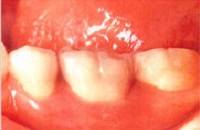

金属が入っている状態

前歯に金属の裏打ちをした歯が入っている状態です。

長年使用していたため、歯と歯ぐきの間に金属が露出してきました。